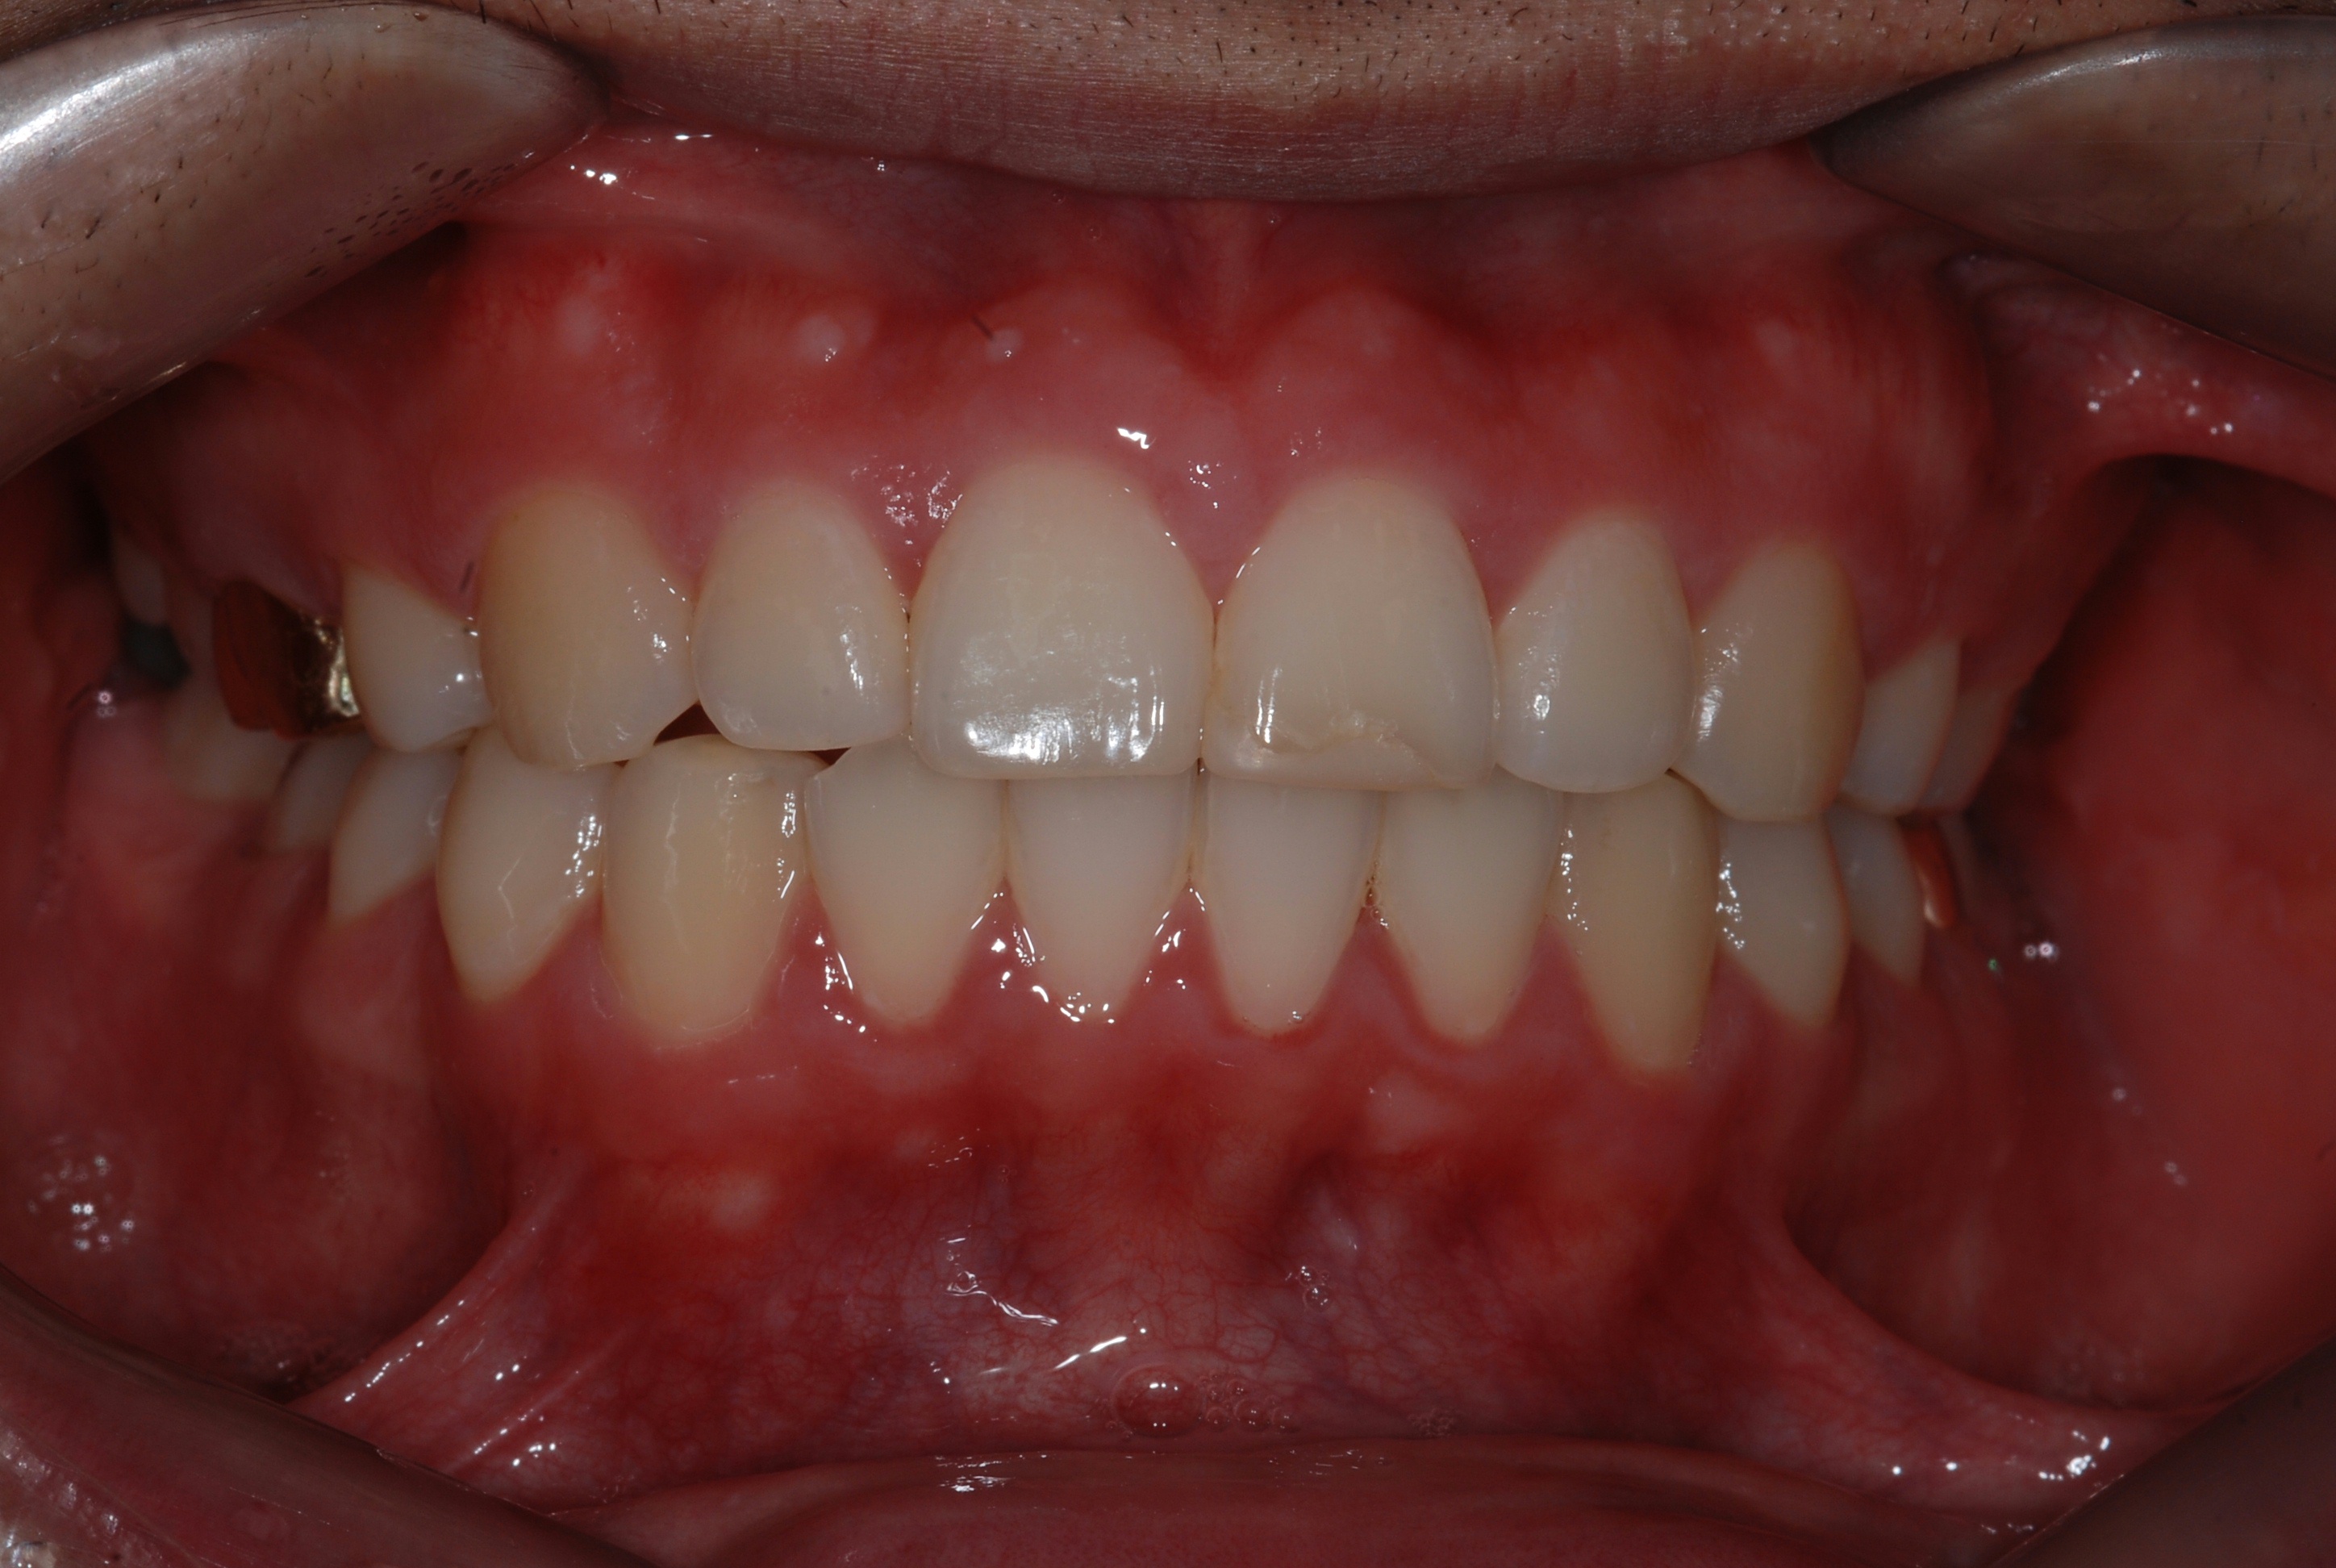

치료 후 사진입니다.